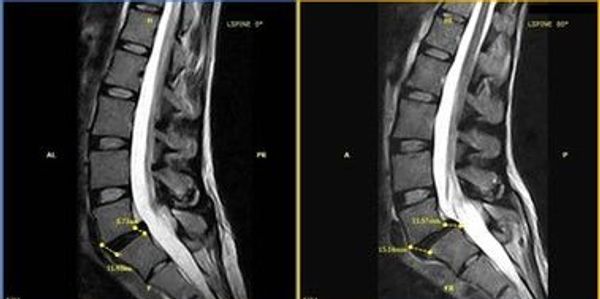

The regions Only Stand up MRI allows you to see your injury with weight.